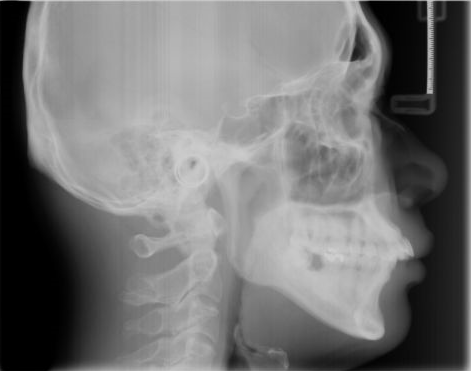

【进行口腔全景片/CT检查】

经过口腔全景片/头颅侧位片和口腔CT检查,正畸大师张超主任诊断:何小姐之所以矫正失败,是因为之前的医生未对其矫正阶段进行准确判断,牵拉过早、频繁加力、力度过大,造成牙齿矫正力度外溢,致使外突。